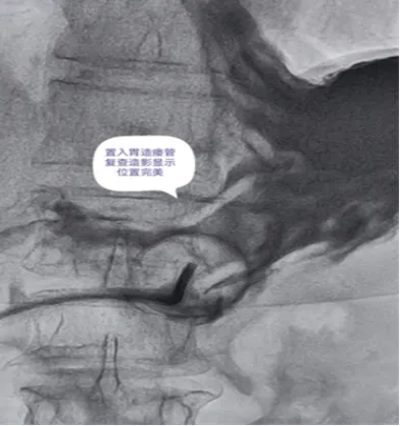

DSA引导下经皮胃造瘘术,是在数字减影血管造影(DSA)这个“透视眼”的实时可视化导航下,于患者腹壁上建立一个仅 3-5毫米 的微小穿刺点。通过这个“针眼”,医生精准地将一根营养管直接置入胃部,建立起一条直达的营养通道。

整个过程就像一次精准的“导航穿刺”,全程操作便捷、创伤小,却能完美替代传统的鼻饲管,为患者提供长期、稳定、安全的营养支持。

DSA影像全程清晰可视化,可精准避开血管、脏器等重要组织,穿刺定位误差小;穿刺创口仅3-5mm,出血量少,术后反流、误吸、肺炎等并发症发生率低于5%,术后1-2天即可正常喂养,恢复速度快。